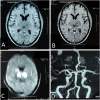

A 35-year-old man with a history of multiple substances abuse (alcohol, tobacco and cannabis) presented with acute, severe, holocranial headache associated with nausea and few episodes of vomiting followed by acute onset Broca-type aphasia with intact comprehension from next day, without any other focal neurodeficits, seizure or altered sensorium. Neurological examination was marked by Broca-type aphasia and failure in convergence reaction bilaterally, rest unremarkable. Brain imaging revealed lesions in bilateral thalamus, while magnetic resonance venography showed multiple flow voids in posterior part of superior sagittal sinus and bilateral transverse sinus. A diagnosis of cerebral venous sinus thrombosis was made. Subsequent investigations revealed decreased levels of protein C, protein S and antithrombin III. The patient was started on anticoagulation to which his headache and aphasia recovered completely after 8 and 12 days of therapy, respectively. He is being continued on anticoagulation and is following-up with us for past 4 months uneventfully.